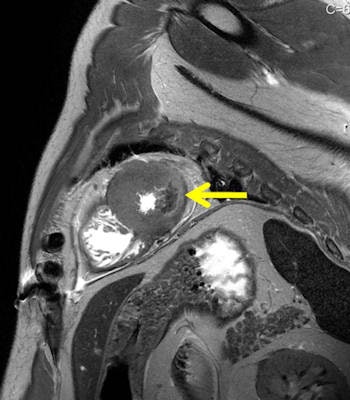

"From the MR point of view, a gunshot to the head is less interesting. With MRI, the gunshot channel is comparably seen as in autopsy, but for pedestrians killed by cars, MR sometimes detects more lesions than autopsy and in sudden cardiac deaths even more than histology can," he said.

Sudden cardiac death happens mainly due to ventricular tachycardia with no direct findings in the heart in autopsy or histology as speed of death leaves insufficient time for recognizable myocardial changes. Jackowski's most recently published study demonstrates that unenhanced MR can show peracute myocardial infarctions even in the absence of a myocardial autopsy finding, and when histology may fail to show ischemic alterations.